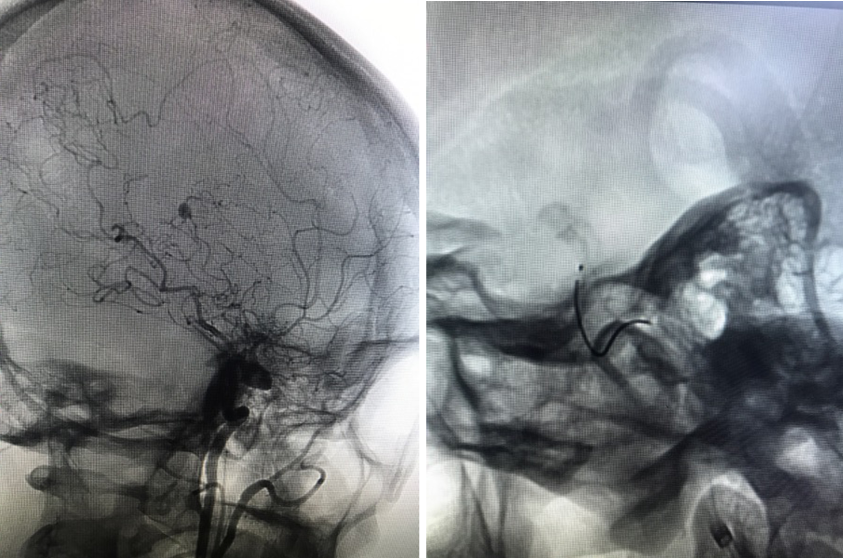

Postop dyna CT(-),GCS15,返回ICU,考虑择期行开颅手术。

术后第一天

早查房时突发意识障碍。

备选方案:

脑室内血肿清除+动脉瘤切除+低流量搭桥。

术后DSA

AN消失

Graft patency

GCS 15,语言及肢体功能良好。

术后CT

在本例病例中,针对脑室内动脉瘤,我们首选血管内治疗栓塞脑室旁动脉瘤,因为血管过于迂曲尝试失败。术后出现脑室内出血,于是启动备选方案,急诊在磁共振导航下通过endoport辅助进行动脉瘤切除,同时部分清除脑室内血肿并放置脑室外引流,降低远期脑脑积水的风险。随着神经内镜的普及,深部的脑血管病变的治疗方案有了更多的选择,而充分的术前评估与周全的手术方案规划是手术安全与成功的基石。